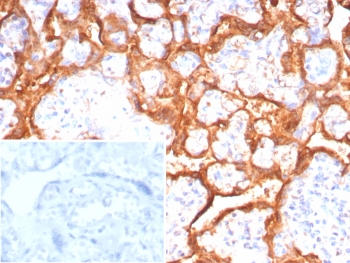

IHC staining of FFPE human placental tissue with Growth Hormone antibody (clone GH/8215R). Inset: PBS used in place of primary Ab (secondary Ab negative control). HIER: boil tissue sections in pH 9 10mM Tris with 1mM EDTA for 20 min and allow to cool before testing.